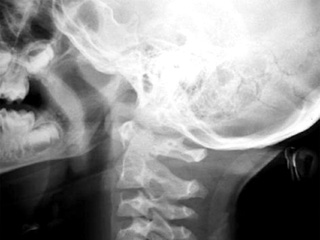

Năm 1970, bác sĩ Robert White đã cấy ghép thành công đầu của của loài khỉ rhesus vào cơ thể của một con rhesus khác. Nhưng ở thời điểm đó các nhà khoa học đã không thể nối đầu với tủy sống làm con vật bị tê liệt dưới điểm cấy ghép.

Theo trang tin UPI, tiến sĩ Sergio Canavero, một thành viên của Nhóm nghiên cứu nâng cao về thần kinh, vừa xuất bản một báo cáo khoa học cho biết giờ đã có công nghệ có thể cấy ghép đầu của một người này vào cơ thể của một người khác.

Phần lớn quy trình cấy ghép lần này được giữ nguyên giống thử nghiệm cũ. Đầu được cấy ghép được ướp lạnh từ 12-15 độ C. Sau đó các bác sĩ phẫu thuật sẽ có 1 tiếng đồng hồ để cùng lúc cắt bỏ 2 đầu và cấy ghép với hệ thống tuần hoàn của cơ thể nhận. Trong suốt quá trình cấy ghép, cơ thể hiến phải được ướp lạnh và tim phải hoàn toàn ngừng đập. Khi đầu đã được nối, tim của cơ thể hiến có thể hoạt động trở lại.

Khi đầu được nối lại, các bác sĩ phẫu thuật tiến hành nối tủy sống. Việc này chưa từng được thử nghiệm trên động vật nhưng trong nghiên cứu của mình, Canavero đã chỉ ra là các nhà khoa học đã kết nối có giới hạn tủy sống của loài chuột. Canavero đề xuất cắt dây cột sống bằng một con dao cực sắc và sau đó nối dây cột sống từ đầu sang cơ thể khác. Ông phỏng đoán rằng các loại nhựa như polyethylene glycol (PEG) có thể được dùng để thực hiện sự hợp nhất này. Chi phí cho một ca cấy ghép đầu ước tính khoảng 13 triệu USD.